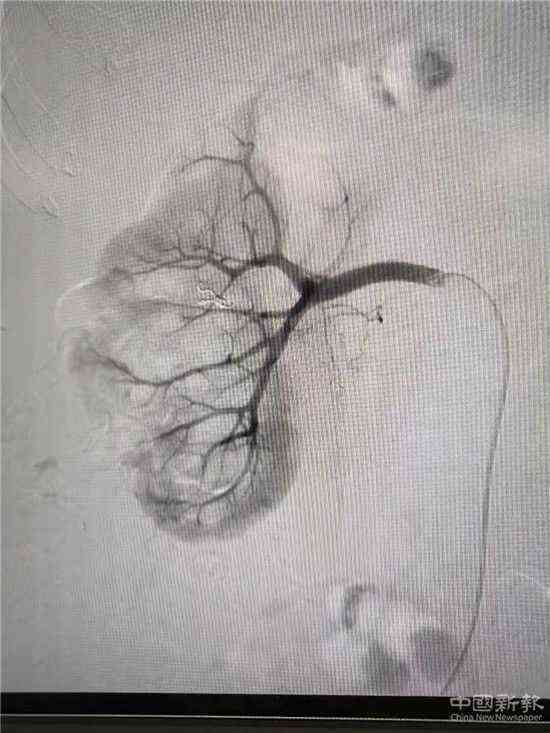

栓塞后造影圖(已止血)

家住湖南省郴州市嘉禾縣廣發(fā)鎮(zhèn)的鄧大媽,因患巨大腎結石進行了“經皮腎鏡取石術”,術后第3天出現(xiàn)大量鮮紅色血尿。經過增強CT檢查,考慮為“腎穿刺口處動脈出血”,醫(yī)院介入血管外科團隊立即為患者在DSA下行“微創(chuàng)介入右腎出血動脈栓塞術”,術后出血立刻停止,尿液由紅色轉為正常顏色。